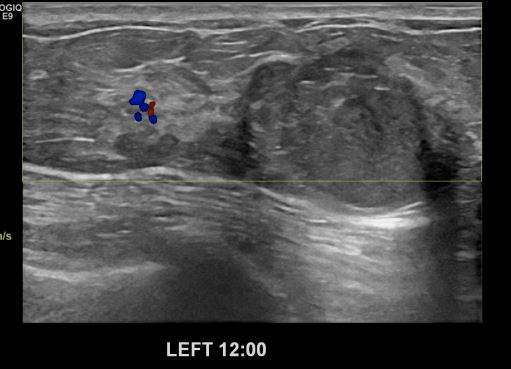

상기환자 60대 여성분으로 내원 보름 전 발견한 유방의 멍울로 초음파 검사 후 왼쪽 유방 12시방향에 위치한 결절 조직검사 시행한 결과 점액암으로 나왔습니다.